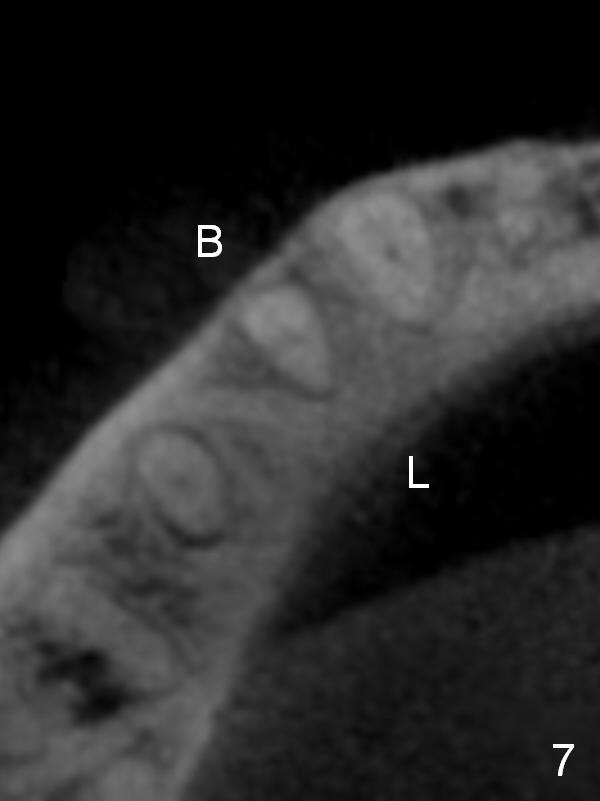

CT sagittal section shows that it is possible to place 4.5x20 mm implant (Fig.6). Axial (Fig.7) and coronal (Fig.9) sections show that the lingual (L) plate is much thicker than the buccal (B) one. To prevent the implant being buccally deviated, a Lindermann bur is used after extraction (black area in Fig.8,10) to remove ~ 1mm bone from the lingual plate (red area in Fig.8,11). A 2 mm pilot drill is placed as lingual as possible (green in Fig.8,11). If the implant (Fig.12) starts to deviate buccally while being placed, remove it from the osteotomy and remove more bone from the lingual plate. Place the implant again and monitor the trajectory tightly.